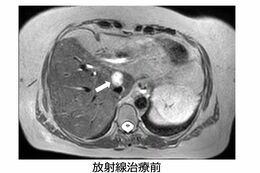

【症例】胆管がん59歳女性(画像提供:GenesisCare)

[写真 3/6枚目] 【症例】胆管がん59歳女性(画像提供:GenesisCare)